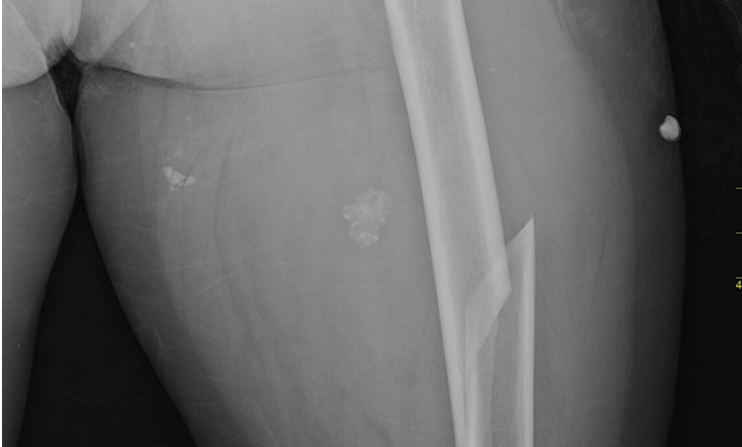

El fémur, el hueso más largo y fuerte del cuerpo humano, conecta la pelvis con la rodilla, siendo esencial para la movilidad. Las fracturas de fémur, aunque menos comunes debido a su resistencia, suelen ocurrir en accidentes graves, como choques de tránsito o impactos violentos.

Esta lesión afecta significativamente la capacidad de movimiento, ya que compromete las articulaciones principales y requiere un largo período de recuperación, además de dejar secuelas permanentes en muchos casos.

Porcentajes de incapacidad según el tipo de fractura

La Tabla de Evaluación de Incapacidades establece los siguientes rangos para fracturas de fémur:

- Fractura de cuello de fémur: 15-20% de incapacidad.

- Fractura de diáfisis femoral consolidada en des eje: 15-20%.

- Luxación traumática de cadera con fractura marginal y necrosis de la cabeza femoral: 20-25%.

- Pseudoartrosis: Entre 40 y 60% (cuello femoral, diáfisis o supracondílea).

A diferencia de otras lesiones, como fracturas de radio o vértebras, la limitación funcional ya está incluida en estos porcentajes, sin necesidad de evaluarla por separado.